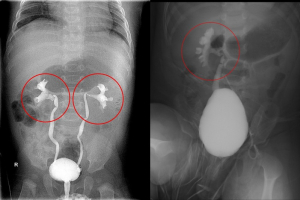

嬰幼兒發燒可能為泌尿道感染 「輸尿管重植」助健康長大

許多家長最擔心孩子突然發燒,而引起小兒發燒的原因,除了常見的感冒,還包含「泌尿道感染」,其中有近三分之一是「膀胱輸尿管逆流」所導致。花蓮慈濟醫院兒童外科楊筱惠醫師指出,尿液逆流不僅容易造成膀胱細菌侵入腎臟,進而起腎盂腎炎及反覆發燒,長期下來也可能產生腎臟疤痕並影響腎功能,甚至有人會因此需要洗腎。